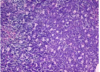

The wall of which cyst?

Periapical Cyst

Open clear areas = Cholesterol clefts where fat

used to be. Multinucleated cells (purple dots)

trying to break down cholesterol